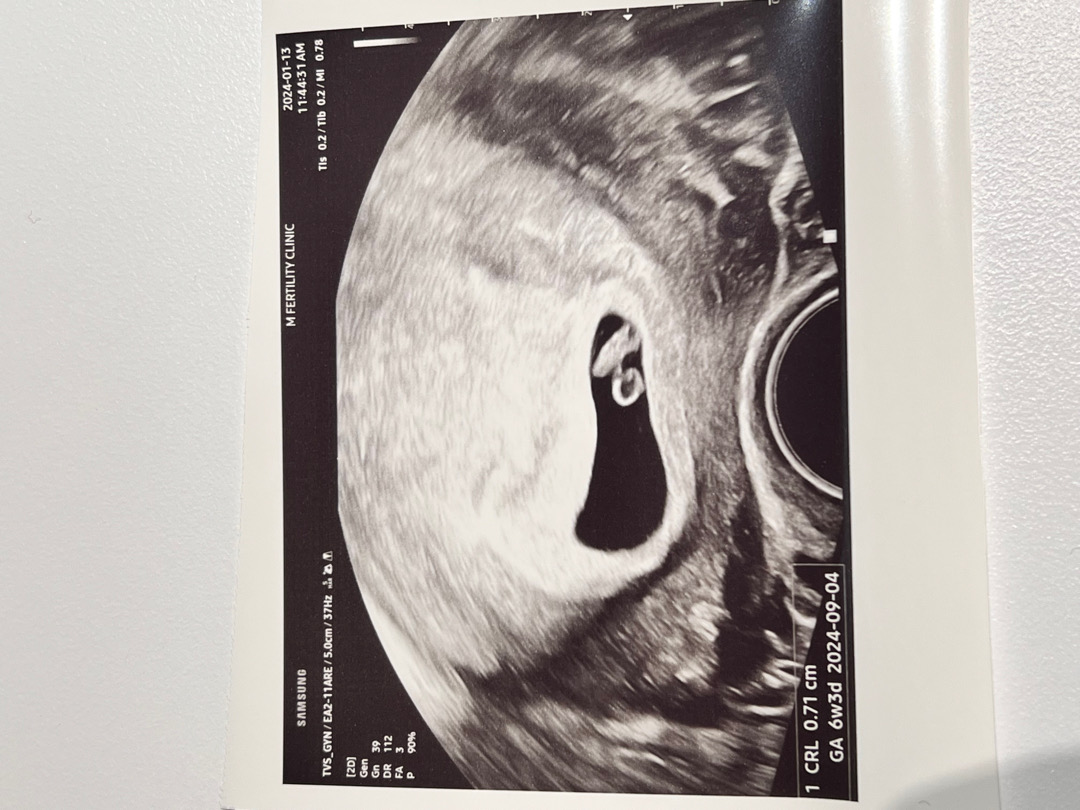

심장소리 듣고 부모님께 임밍아웃!(6주6일)

6주4일에 병원갔어요 애기 길이 0.71cm! 심박수는 124bpm 나왔네요 ㅎㅎ 심박수 듣고 얼마나 눈물이 나던지 병원 나와서도 계속 울었어요ㅠㅠ 양가 부모님께도 임밍아웃했는데 아빠가 그렇게 우시네요ㅠㅠ ㅋㅋㅋㅋ 초음파 영상 어플로 볼수있게 해주는 분만병원으로 전원을 하고 싶은데 8주차 피검까지 하고 옮기면 되겠죠?